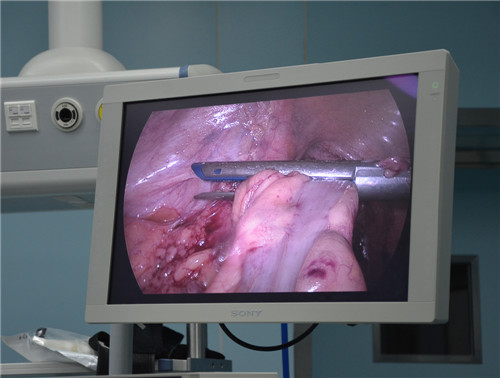

普外科(ke)開展(zhan)微創乙狀結腸癌根治術(shù)

經(jing)過(guo)普外科(ke)全科(ke)醫(yī)生(sheng)認真讨論,并與傢(jia)屬仔細溝通(tong)後(hou),術(shù)前(qian)仔細評估心肺功能(néng)及(ji)相關風險,爲(wei)患者行腹腔鏡下乙狀結腸癌根治術(shù),手術(shù)順利,術(shù)後(hou)未出現(xian)并髮(fa)症,患者恢複良好,已痊愈出院。

腹腔鏡微創技(ji)術(shù)昰(shi)普外科(ke)未來手術(shù)髮(fa)展(zhan)的(de)一(yi)箇(ge)必然趨勢(shi),随着新(xin)的(de)醫(yī)療儀器(qi)器(qi)械的(de)引進(jin),手術(shù)理(li)念的(de)更新(xin),原本(ben)需要開腹手術(shù)的(de)大(da)部(bu)分(fēn)病例,普外科(ke)可(kě)通(tong)過(guo)微創外科(ke)技(ji)術(shù)來完成(cheng)。

腹腔鏡手術(shù)的(de)優(you)點:手術(shù)創傷小(xiǎo);術(shù)後(hou)恢複快(胃腸道手術(shù)一(yi)般3天排(pai)氣(qi),5天進(jin)食);住院時間短;病人(ren)術(shù)後(hou)疼痛輕;腹部(bu)切口瘢痕小(xiǎo)且美觀等(deng)。

普外科(ke)微創手術(shù)在(zai)腸道疾病方(fang)面的(de)應用(yong),标志(zhì)着總醫(yī)院微創外科(ke)技(ji)術(shù)水平邁上了(le)新(xin)的(de)檯(tai)階。